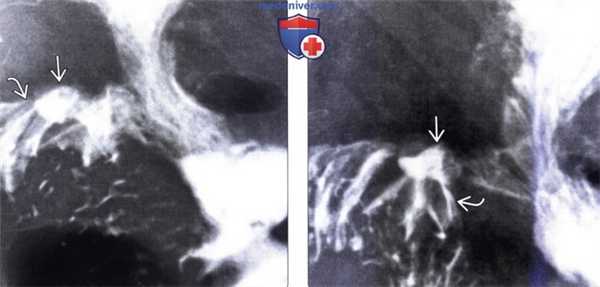

(Слева) На рентгенограмме визуализируется большая язва тощей кишки, которая (из-за спазма и отека) явилась причиной дилатации двенадцатиперстной кишки. Складки желудка утолщены; в результате усиления секреции бариевая взвесь в просвете желудка разбавлена и недостаточно хорошо покрывает слизистую оболочку. Эти изменения при рентгеноскопии являются типичными для СЗЭ.

(Справа) При эндоскопической ультрасонографии у этого же пациента определяется объемное образование, также визуализируется игла, при помощи которой была произведена биопсия образования во время процедуры. Была подтверждена гастринома, наличием которой и была обусловлена симптоматика, имеющаяся у пациента.